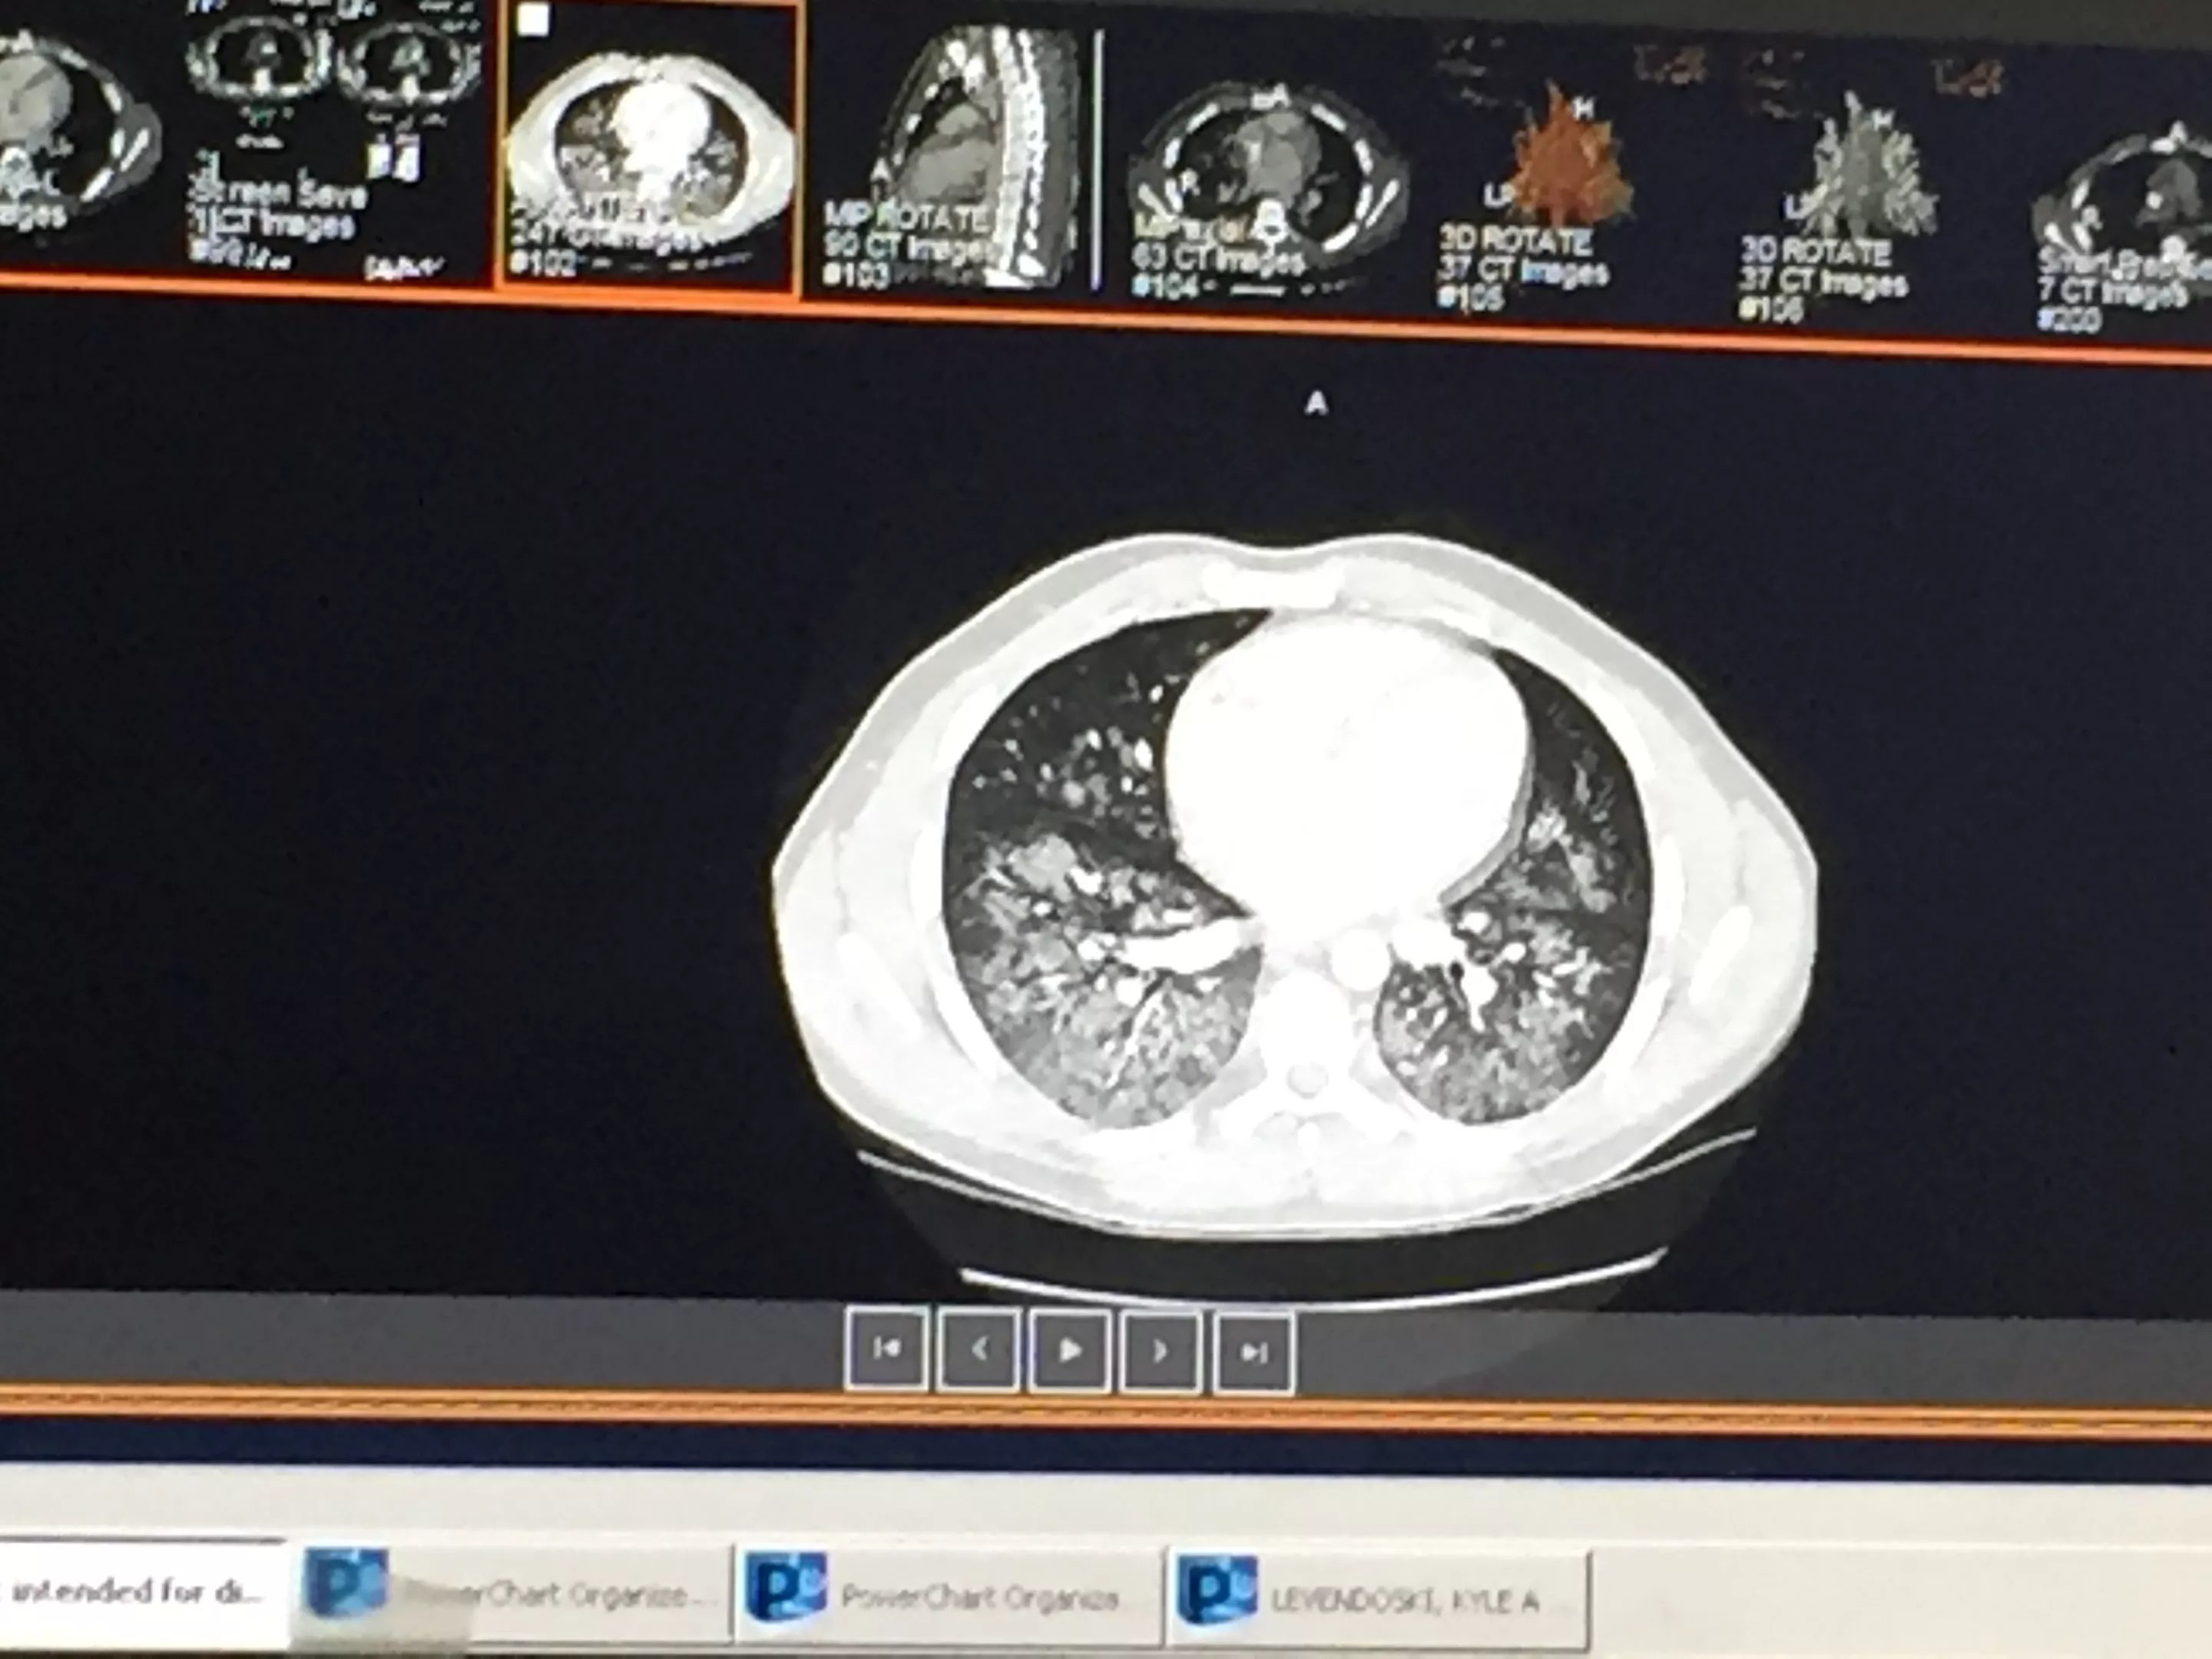

From his hospital bed, Levendoski watched news footage of others who had come down with similar pulmonary illnesses. He began comparing the images of those patients’ lungs with his own. “I looked on my phone to see how my lungs looked and how theirs looked. Mine looked worse!”